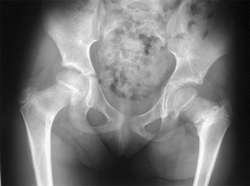

Figure 27.1

The radiographic appearance of congenital coxa vara in an 18-month-old child with a congenital short femur. (Courtesy of Perry L. Schoenecker.) |